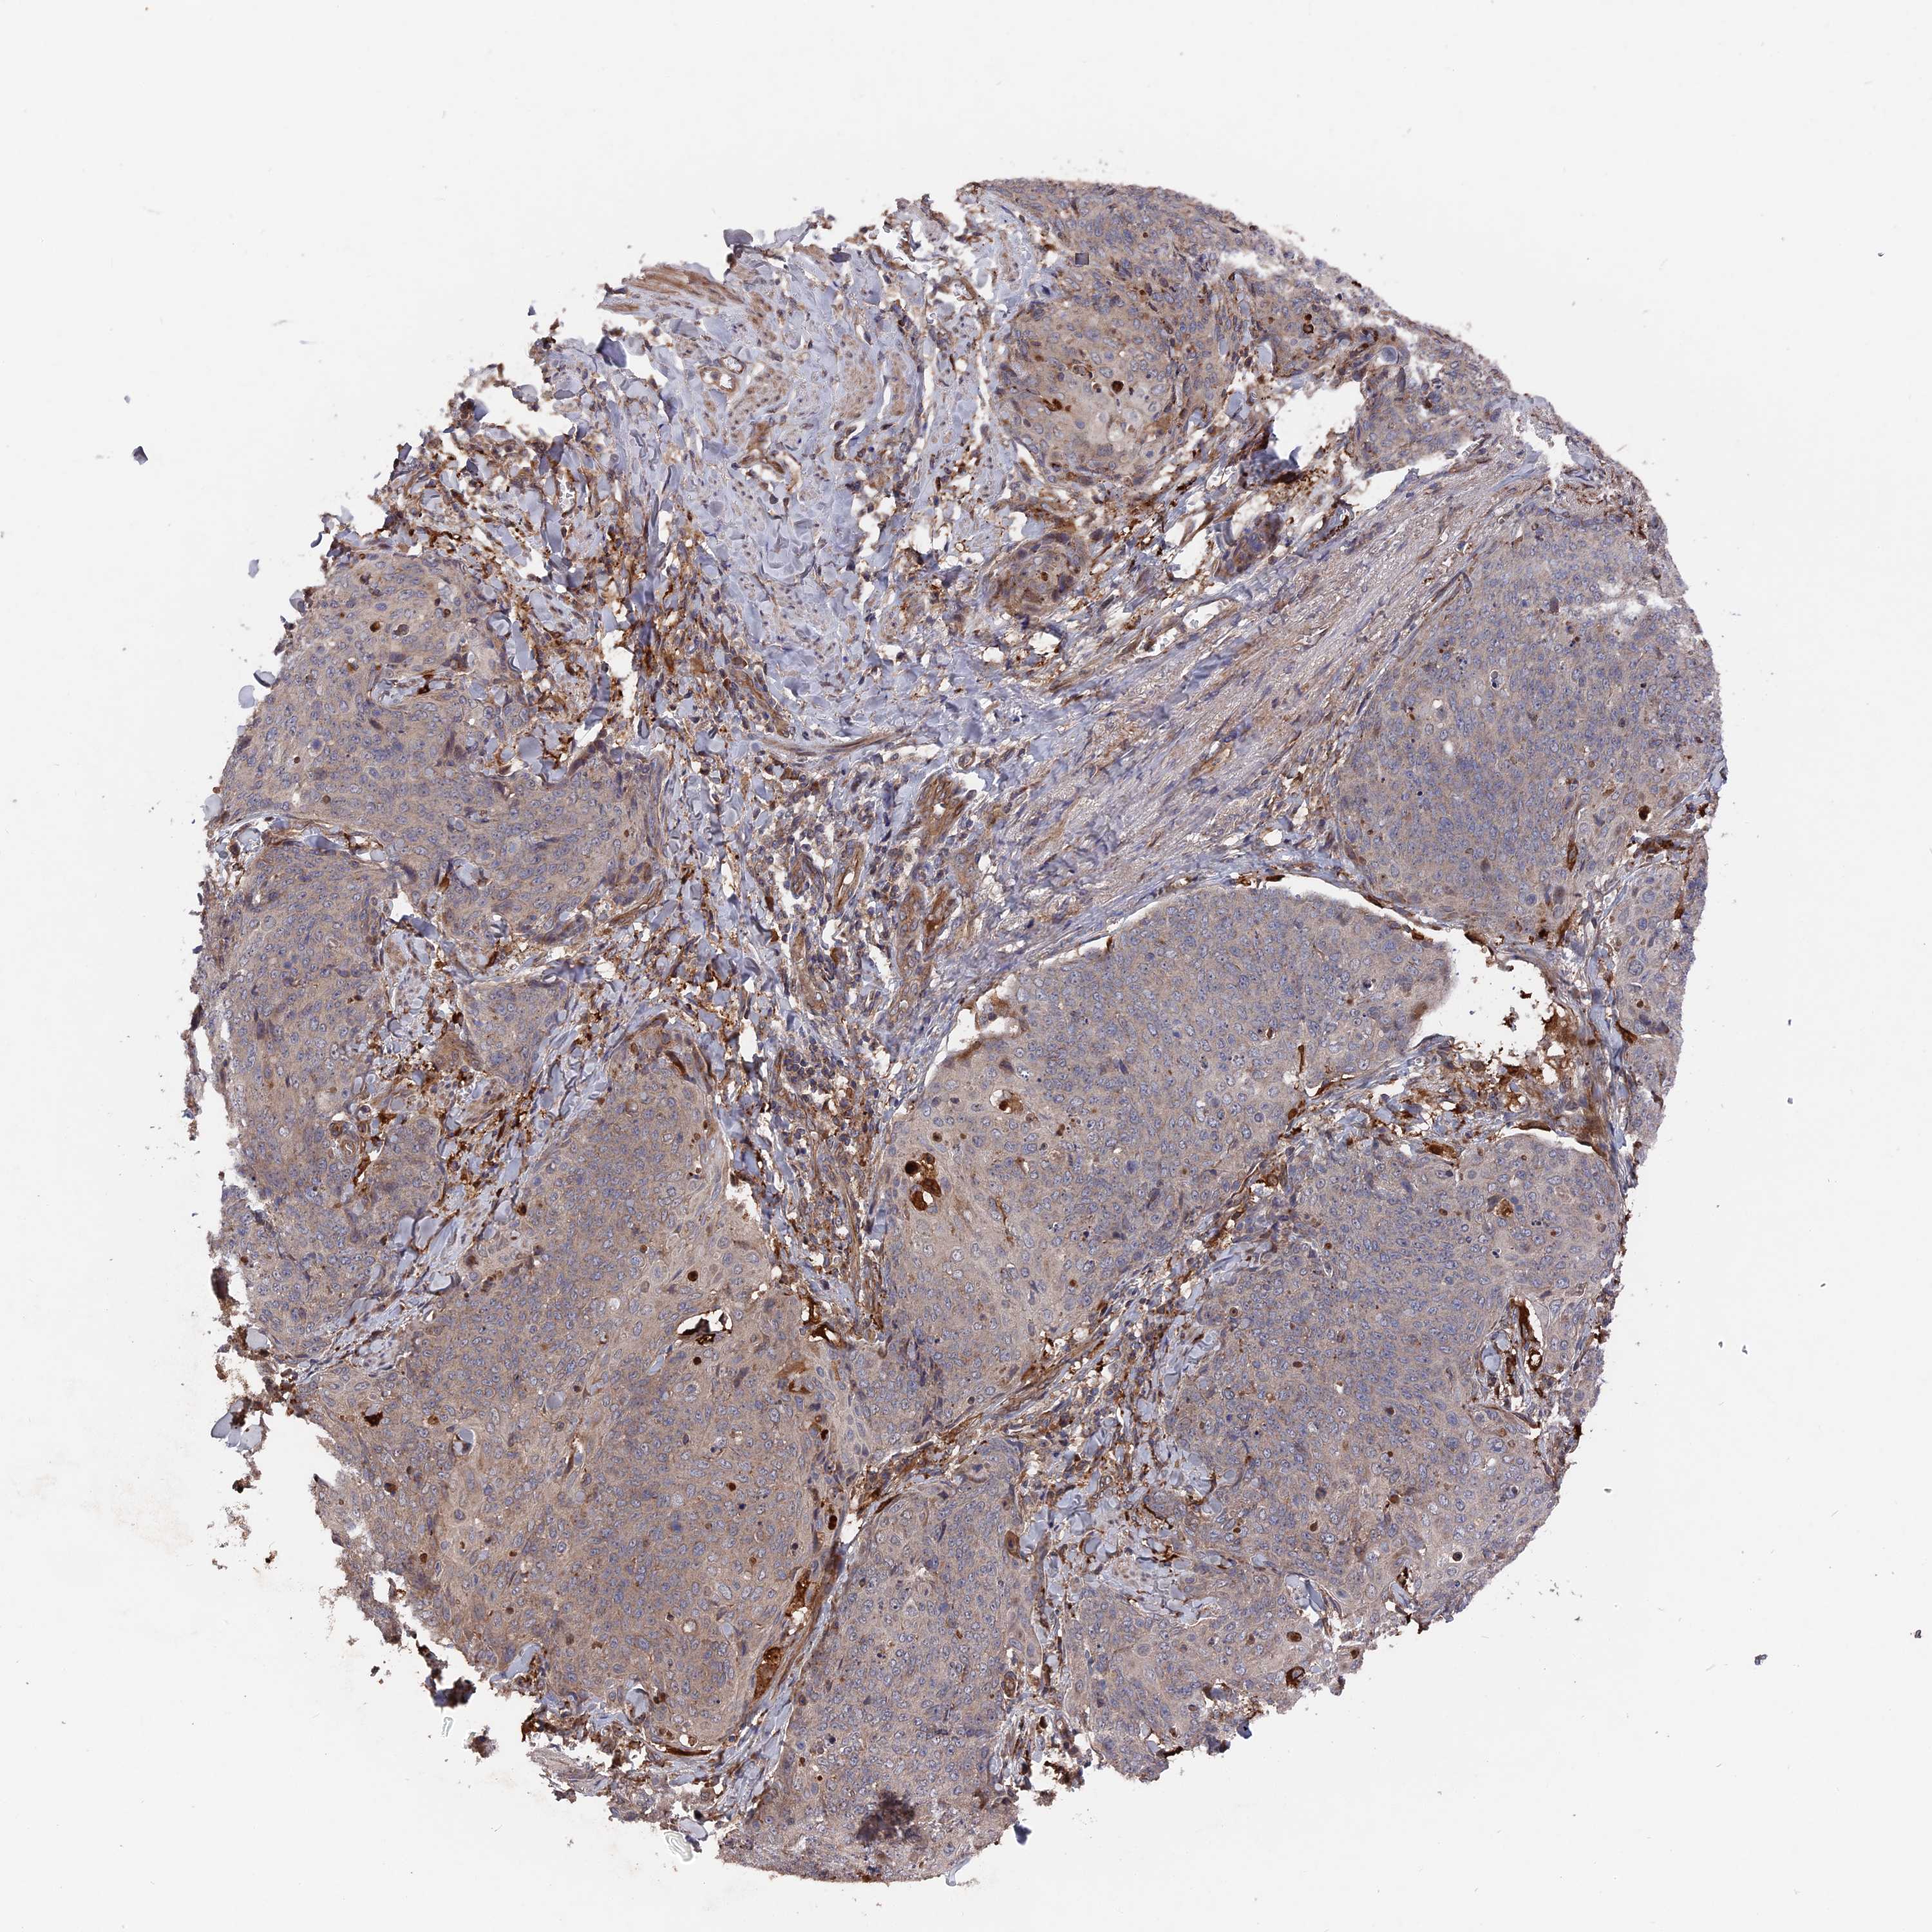

SKIN CANCER - Protein expressioni

A mouse-over function shows sample information and annotation data. Click on an image to view it in a full screen mode. Samples can be filtered based on level of antibody staining by selecting one or several of the following categories: high, medium, low and not detected. The assay and annotation is described here.

Each image is clickable and will lead to virtual microscopy that enables deeper exploration of all samples and also displays staining intensity scores, fraction scores and subcellular localization as well as patient and tissue information for each sample.

Antibody HPA041745

Staining

High

Medium

Low

Not detected

Intensity

Strong

Moderate

Weak

Negative

Quantity

>75%

75%-25%

<25%

None

Location

Nuclear

Cytoplasmic/membranous

Cytoplasmic/membranous,nuclear

Basal cell carcinoma